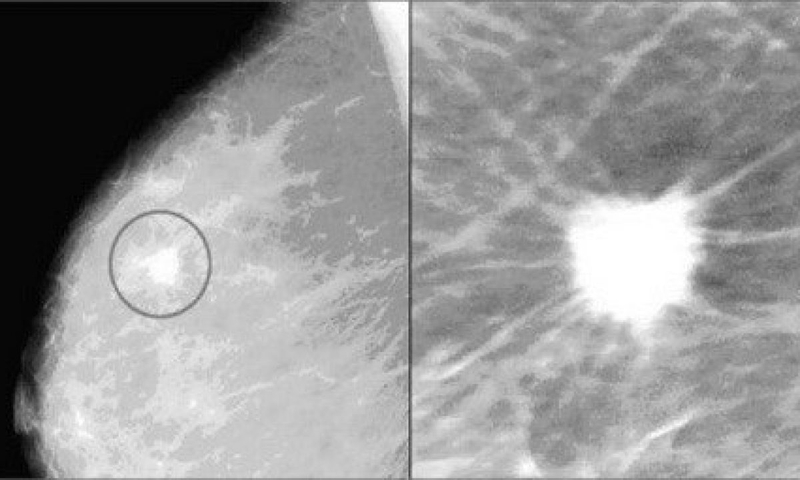

Khối u tiểu thùy thường không gây ra bất kỳ triệu chứng nào hoặc không thấy được trên phim chụp nhũ ảnh. Bệnh thường được phát hiện ra trong khi thực hiện sinh thiết hoặc xét nghiệm khác vì có triệu chứng hoặc thay đổi bất thường ở vú. Ví dụ, khi vôi hóa (các đốm vôi nhỏ) được phát hiện trên phim chụp nhũ ảnh.

/https://cms-prod.s3-sgn09.fptcloud.com/4_5_1200x720_5ba4e1ed7b.jpg) Ảnh chụp vôi hóa vú

Ảnh chụp vôi hóa vúKhông có bất kỳ điều trị chuẩn nào cho hình thành khối u tiểu thùy. Bác sĩ chuyên khoa sẽ thảo luận các lựa chọn điều trị với bạn và tìm ra phương án thích hợp nhất dựa trên từng trường hợp.